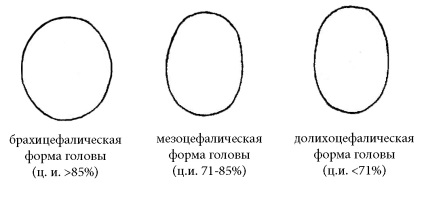

Să începem cu faptul că toți oamenii au structura anatomice individuale, cum ar fi diferite forme ale craniului. Capul poate fi alungit din față spre spate și părțile laterale conice și poate avea o față largă și o mică parte din dimensiunea fronto-occipital. Pentru a determina forma exactă a capului fetal există un indicator cum ar fi indicele cefalic. Este dimensiunea raportul biparientalnogo (BDP) la fronto-occipital (LZR) și este adesea exprimată ca procent. Cei mai mulți oameni au forma mezotsefalicheskuyu a capului, pentru care indicele cefalică variază în mod normal, 71-85%, astfel încât acest interval este considerat a fi mediu. Dar, caracteristici care merg dincolo de ea nu este o anomalie mic, dar numai structurale. Dacă indicele cefalic este mai mică decât 0,71, o astfel de formă a capului se numește dolihotsefalicheskoy. și în cazul în care mai mult de 0,85 - pentru brahicefale.

indicele cefalic nu contează cu adevărat, așa că nu este de obicei masurata prin ultrasunete. Este de notat faptul că forma capului fatului poate depinde de poziția sa în uter. Deci, dolihotsefalicheskaya forma capului este comuna in prezentare pelviana. În cazuri foarte rare, merge dincolo de indicele cefalică gama medie poate fi unul dintre semnele „moi“ de anomalii cromozomiale.